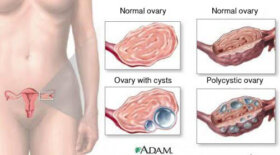

오늘 이 글에서는 여성이 알아야 할 난소낭종에 관해 살펴볼 것이다. “낭종”은 인생에 걸쳐 생식계에 영향을 미치는 가장 흔한 질환 중…